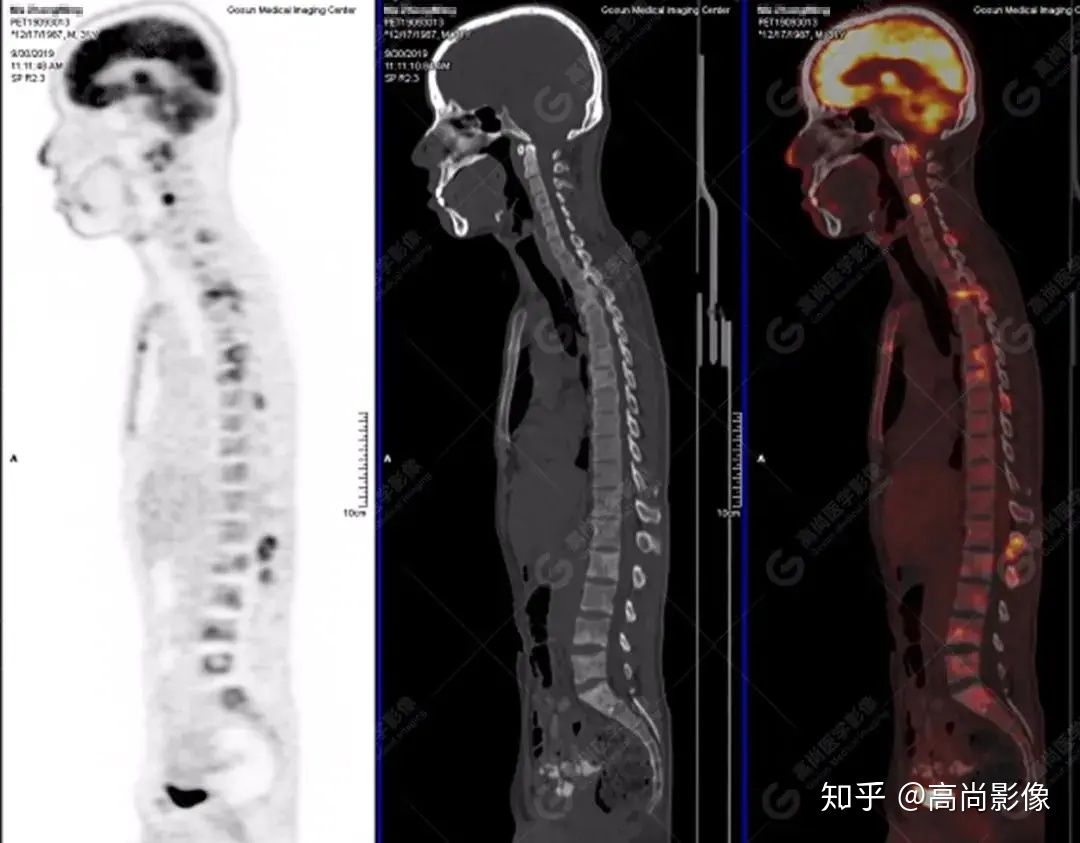

脊柱多發(fā)椎體及附件骨質(zhì)破壞,代謝不均性增高

【PET/CT提示】雙肺、左側(cè)胸膜多發(fā)結(jié)節(jié)影,全身多處骨質(zhì)破壞,全身多發(fā)淋巴結(jié)腫大,代謝攝取不均勻性增高。

2.全身多系統(tǒng)、多形態(tài)、多發(fā)病灶(肺部、胸膜、淋巴結(jié)、骨),18F-FDG攝取不均性增高;

特征:肺部病灶簇狀分布,上葉尖段及下葉背段為著;腫大淋巴結(jié)分布不對稱,無融合、中央有壞死改變,與淋巴瘤、轉(zhuǎn)移瘤等有一定的鑒別診斷意義;